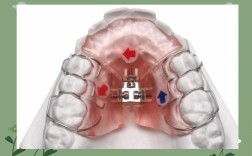

牙齿矫正是通过外力引导牙齿、颌骨及周围组织改建,最终实现咬合功能与面部美观协调的医疗过程,矫正器作为核心工具,根据作用机制可分为固定矫正器、活动矫正器及功能矫正器等,其中功能矫正器因其在调节颌骨发育、改善口腔肌功能方面的独特优势,在儿童及青...